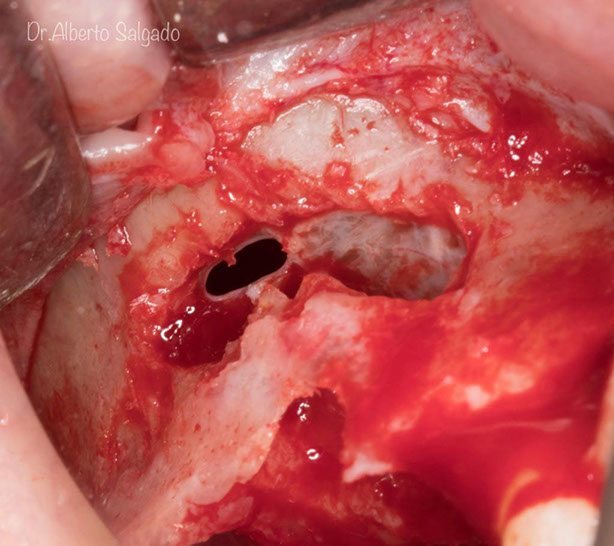

Dr. Alberto

Salgado